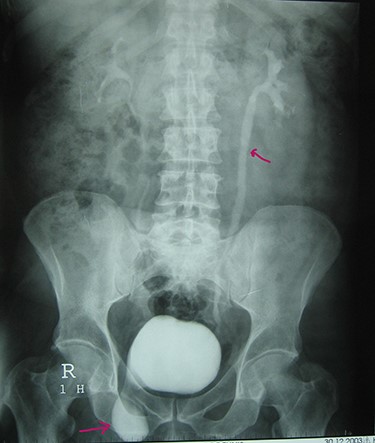

A 72-year-old man with a history of controlled diabetes and hypertension presented to our department with right inguinal swelling and intermittent lower urinary tract symptoms (LUTS) with pollakiuria, dysuria, prolonged micturition time and a sensation of a full bladder after micturition. He reported nausea, vomiting and right lower quadrant paint. The patient also reported having to manually compress the scrotum in order to empty the bladder. Physical examination revealed a slightly painful on palpation and reducible 6 cm right inguinal hernia extending into the right hemiscrotum. The body mass index of the patient was 31.4 kg/m2. His PSA was 4.3 ng/ml. On uroflowmetry, maximum flow rate (Qmax) was 13 ml/s and the voided volume was 180 cc. The uroflow curve was flat. The Bacteriological examination of urine was negative. Retrograde urethrocystography revealed right inguinal hernia containing a portion of the urinary bladder (Figs 1,2). He also had an intravenous urography in order to study the upper urinary tract and to have an idea of the renal function. This radiological exploration confirms the data of the retrograde urethrocystography and illustrates well the bladder hernia. However, a moderate left hydronephrosis with a nonobstructive pyelic calculus of 1.5 cm was observed on intravenous urography (Figs 3,4). Intraoperative findings revealed a direct right inguinal hernia with complete herniation of bladder into the scrotum. The bladder appeared healthy with no signs of injury and was restored to its normal anatomical position without resection. The hernia was repaired with a biologic mesh by the Lichtenstein technique. The patient had an uneventful postoperative course. Concerning his pyelic calculus problem, shock wave lithotripsy sessions were scheduled.

Intravenous urography: moderate left hydronephrosis and bladder addition image.